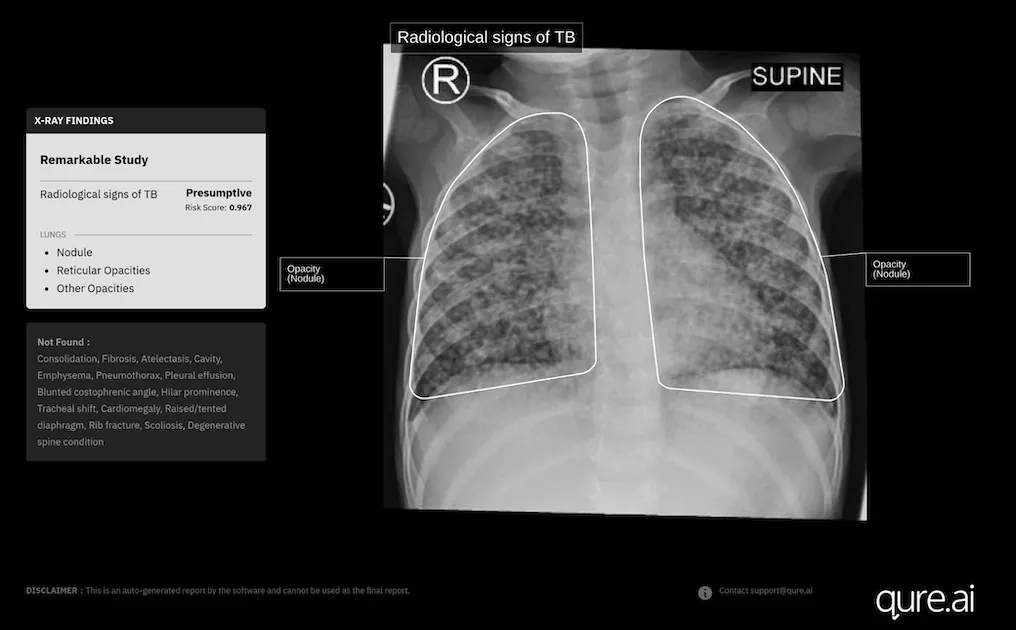

Photo courtesy of Qure.ai

Indian medical imaging AI company Qure.ai has secured new approval in Europe for the expanded use of its chest X-ray analysis AI tool to diagnose paediatric tuberculosis in toddlers.

It has recently received a new CE Mark under the European Union's Medical Device Regulation for the use of its AI-powered chest X-ray software, qXR, in children aged 0-3 years.

Last year, Qure.ai further trained qXR with more paediatric data – chest X-rays from children aged 0-15 years paired with corresponding GeneXpert results collected from several high TB-burden countries.

"We gathered thousands of these X-rays and retrained the model to capture the subtle and often non-specific patterns seen in younger children, particularly those under five," Divya Gupta, Chief Business Officer – Global Health at Qure.ai, told Mobihealth News in an email interview.

The model demonstrated a "marked increase in accuracy across all paediatric groups," she noted. Retrospective and prospective studies done after an internal validation and initial deployments at select global sites also showed "highly encouraging results." Qure.ai is set to report findings from a large-scale internal validation at a global conference on lung health in Denmark later in November.

"Preliminary analyses from earlier test sets have already shown a 20% improvement in diagnostic accuracy against GeneXpert results after incorporating paediatric data into the model," Gupta added.